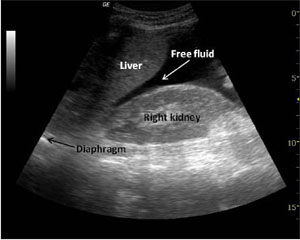

Prehospital ultrasound has a major role to play in the same way. In the setting of trauma, a postive prehospital FAST scan may, for example, mean the patient is met in resus by the trauma consultant while an OR is being made ready, instead of the trauma team being represented in resus by the junior surgical registrar (Note – no disrespect is meant towards junior registrars here, we have all been there!) Minh Le Cong recently tweeted about a patient who had an in-flight scan demonstrating a ruptured ectopic pregnancy. ED was bypassed and the patient went straight to threatre – the ultimate in streamlined care!